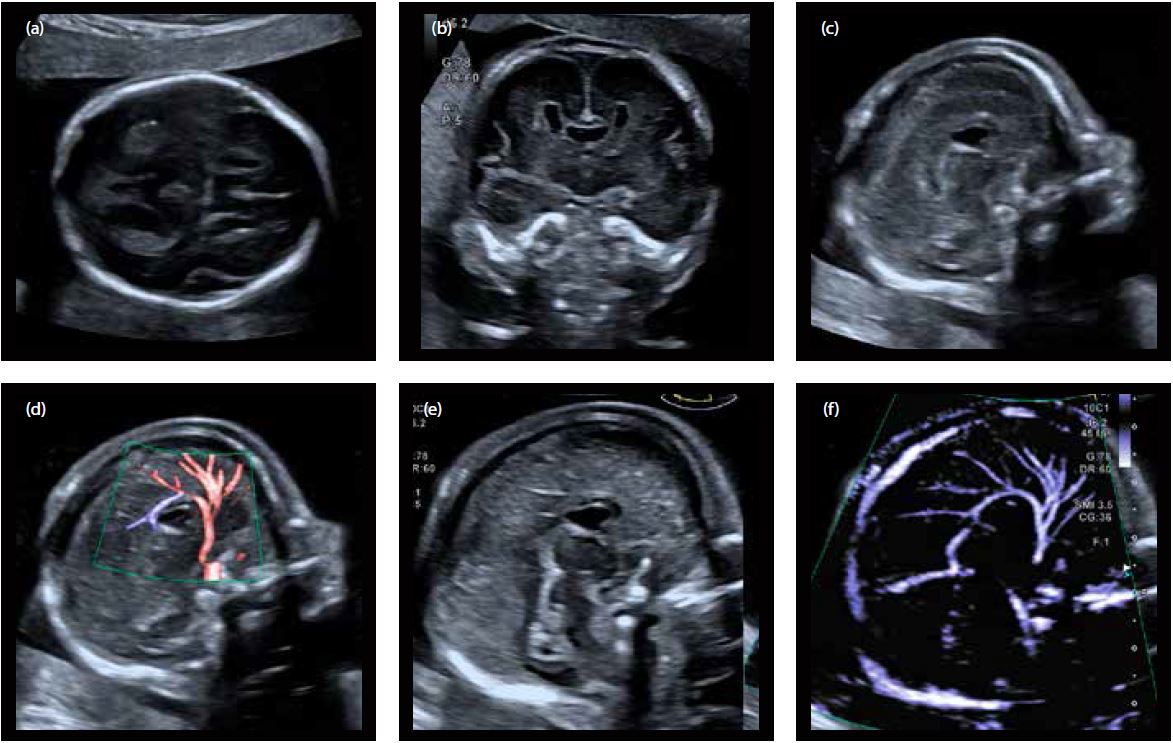

Використання високочастотного конвексного датчика виявилося дуже корисним при дослідженні аномалій мозолистого тіла (повна агенезія, часткова агенезія). Він дозволяє отримати високу деталізацію при дослідженні середньої частини та навколишніх структур головного мозку (паренхіми головного мозку, кори головного мозку) і дає дійсно інформативні зображення (мал. 3 і 4).

Малюнок 4 Часткова агенезія мозолистого тіла:

a) Аксіальний зріз головного мозку плода (наявність дисморфічної cavum septum pellucidum)

b) Корональний зріз головного мозку плода (наявність дисморфічної cavum septum pellucidum)

c) Сагітальний зріз головного мозку: мозолисте тіло видно тільки в передніх відділах (відсутність валоку)

d) Серединний сагітальний зріз з ADF

e) та f ) Подвійне вікно з серединним сагітальним зрізом, що візуалізує передню частину мозолистого тіла та застосування технології SMI, яка дозволяє оціники аномальну довжину перікальлозальної артерії